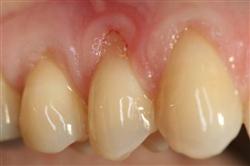

Cosmetic Soft Tissue Grafting

In addition to the functional problems previously mentioned, receding gums can look unsightly.

Longer looking teeth and exposed tooth roots give an "old" appearance to your smile. Some people cover their mouths when they smile for this very reason.

Cosmetic Soft Tissue Grafting can add a new youthful appearance to your smile. In your initial consultation with Dr. Hoidal, he will thoroughly explain what can be achieved in your particular case.